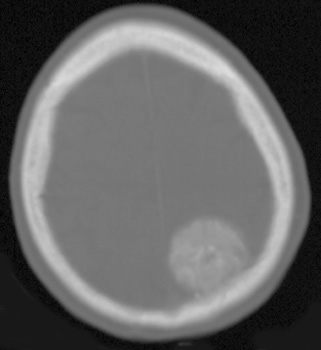

Head CT > Tumor > Meningioma

Meningioma

Meningiomas are the most common extra-axial neoplasm of the brain. Middle-aged women are most frequently affected. Twenty percent of meningiomas calcify. On CT, meningiomas are usually isointense to gray matter.

![]() Bone windows confirm calcification within the mass. ![]() Axial, post contrast CT demonstrating broad based enhancing extra-axial mass. |